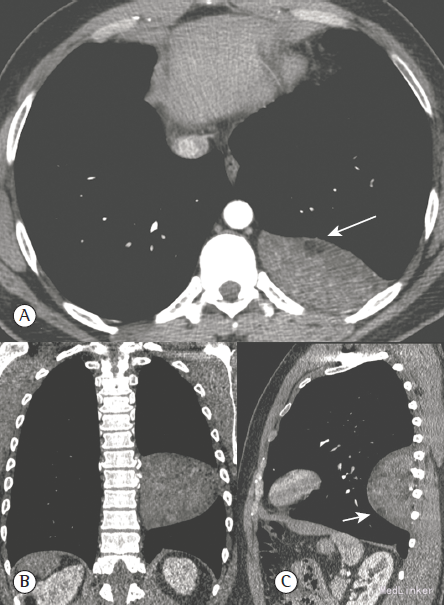

查体及实验室检查均未见异常。胸片提示左下胸廓巨大不透亮影。胸部CT提示为左下胸密度不均匀胸膜肿物(图1)。该肿物为来源于胸壁的肺外肿物,未见钙化。